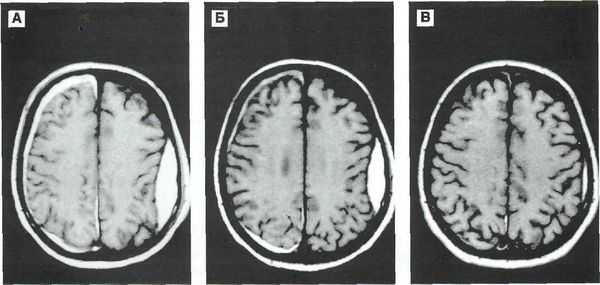

- КТ головного мозга. Как правило, на томограммах внутримозговая гематома имеет вид очага гомогенной плотности округлой или овальной формы. Если гематома сформировалась в результате ушиба головного мозга, то она обычно имеет неровный контур. С течением времени происходит уменьшение плотности гематомы до изоплотного состояния, при котором ее плотность соответствует плотности мозговой ткани. Для малых гематом этот период составляет 2-3 недели, а для средних — до 5 недель.

- МРТ головного мозга. При уменьшении плотности гематома лучше визуализируется при помощи МРТ, хотя в начальном периоде применение МРТ может привести к ошибочному диагнозу в пользу опухоли с кровоизлиянием. Поэтому, при наличие такой возможности, многие неврологи и нейрохирурги предпочитают использовать в ходе диагностики оба способа нейровизуализации (КТ и МРТ).

Врач может определить приблизительный возраст гематомы по снимкам компьютерной и магнитно-резонансной томографии (КТ и МРТ). От срока давности зависит выбор методов лечения.